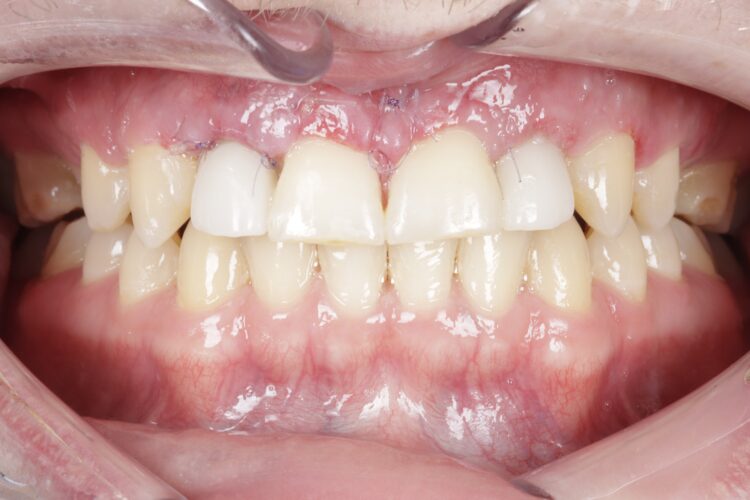

Case outcome

Both the patient and I were very happy with the outcome in this case. Given the patient’s reluctance towards excessive treatment, he was not willing to undergo any further procedures such as composite edge bonding or veneers, which could have enhanced the aesthetic result. However, he was more than satisfied with the replacement of his missing lateral incisors, and while he understands that more implants will be needed in the future when the remaining deciduous teeth are lost, he was happy to postpone that treatment for now.

This case presentation shows a real-life result of the kind of treatment we deliver every day in our clinic. It also demonstrates how a guided workflow allows us to place implants exactly as planned, making the process easier and more efficient.